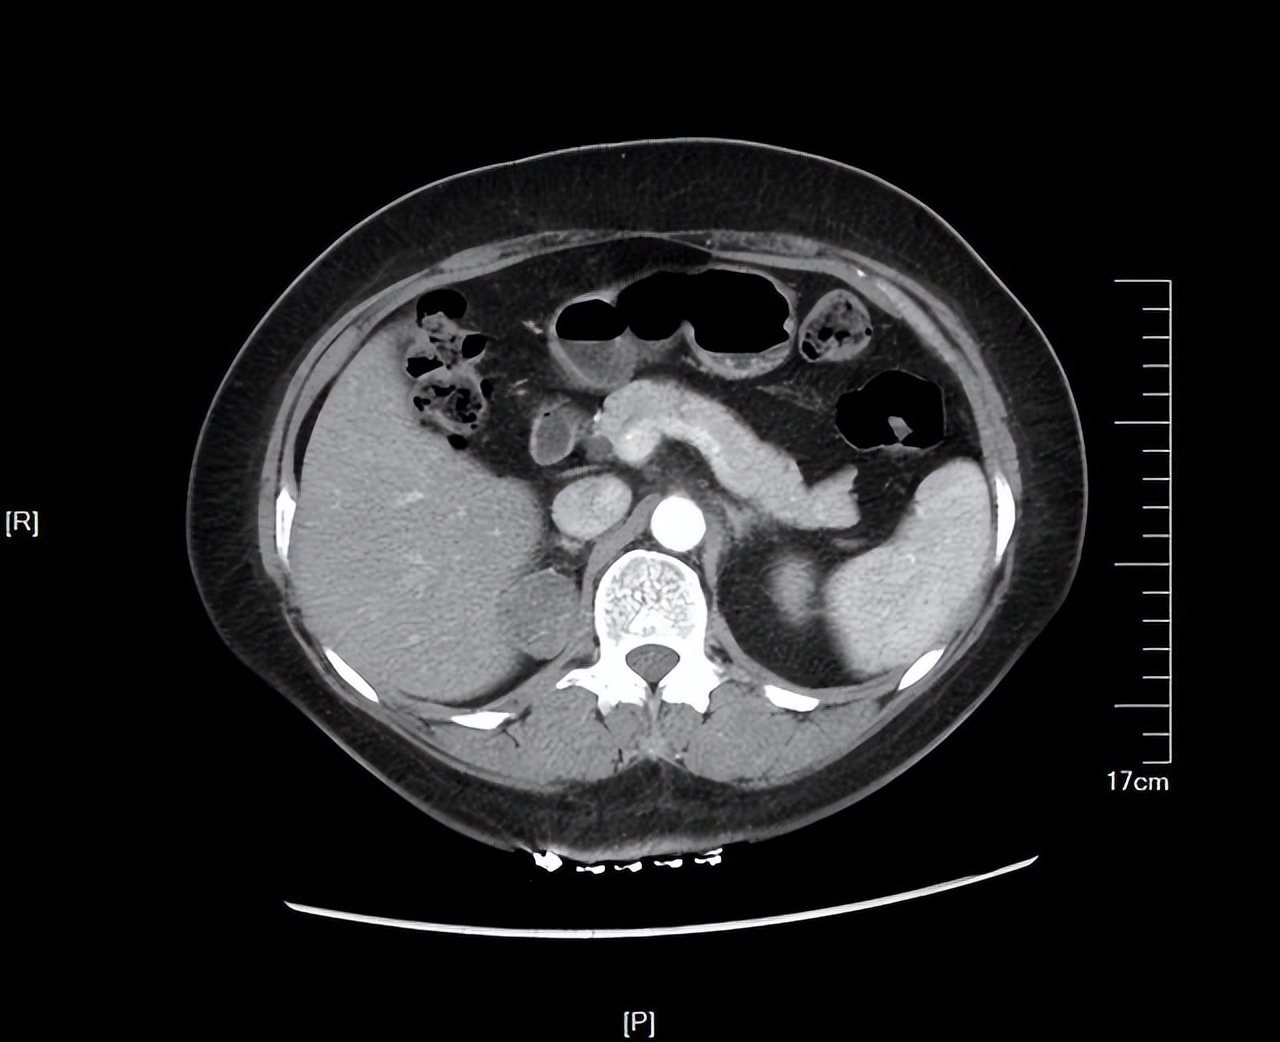

3、膀胱癌的分期:多采用TNM 分期标准分为: Tis 原位癌,T。无浸润的乳头状癌,T1 漫润膜固有层,T2: 漫润肌层,又分为T2a漫润浅肌层(肌层内1 /2),T2b 漫润深肌层(肌层外1 / 2); T3 润膀胱周围脂肪组织,又分为T3 a 显微镜下发现肿瘤侵犯膀胱周围组织;T3b 肉眼可见肿瘤侵犯膀胱周围组织,T 4;浸润前列腺、子宫、阴道及盆壁等邻 近器官。淋巴结转移情况分为Nx 淋巴结转移无法评估,N1 (真骨盆区)单个淋巴结转移 N2多个淋巴结转移,N3 总血 管旁淋巴结转移。 远处转移情况: Mx无法评估是否远处转移,MO 无远处转移,M1远处转移。

4、膀胱癌的治疗: 以手术治疗为主。根据肿瘤的临床分期、病理并结合病人全身状况,选择合适的手术方式。 原则上Ta 、T 及局限的分化较好的T2 期肿瘤,可采用保留膀胱的手术。T期原则上Ta 、T 及局限的分化较好的T2 期肿瘤,可采用保留膀胱的手术。a、T1: 期肿瘤,以经尿道膀胱肿瘤切 除术(常称电切手术 )为主要治疗方法。如无电切设备,可作膀胱开放手术。为预防肿瘤复发,术后可采用膀胱内药物灌 注治疗。